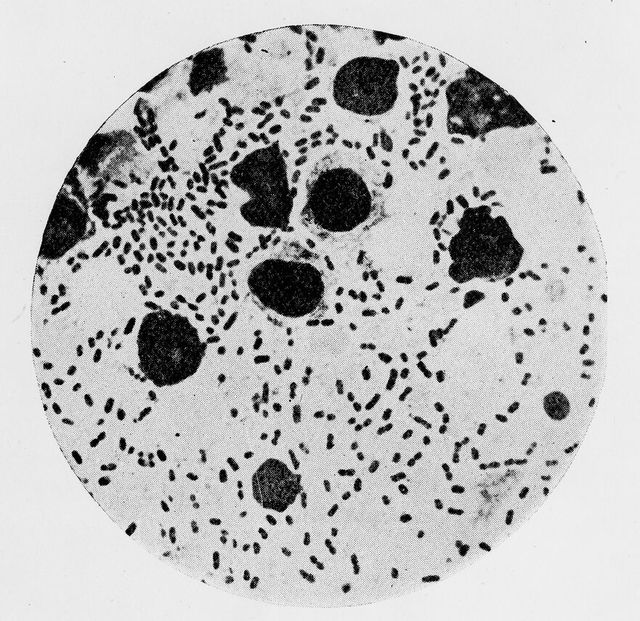

M0014321: Pasteurella pestis, the bacteria causing bubonic plague

Credit: M0014321: Pasteurella pestis, the bacteria causing bubonic plague. Source: Wellcome Collection.